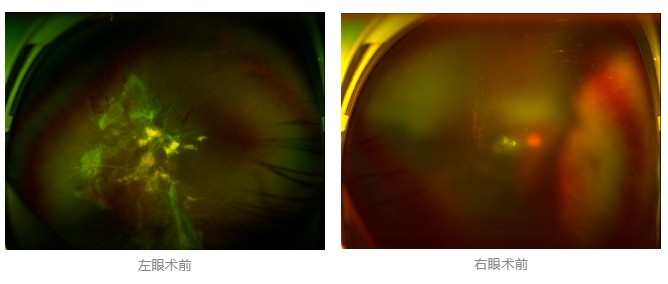

經(jīng)廈門眼科中心眼底病專科行政主任王曉波檢查后,確診其雙眼糖尿病視網(wǎng)膜病變VI期,伴發(fā)雙眼視網(wǎng)膜脫離和黃斑水腫,且右眼視網(wǎng)膜上增殖膜叢生,若再不盡快進(jìn)行治療,恐有失明風(fēng)險(xiǎn)。

面對(duì)陳先生的復(fù)雜病情,王曉波主任采用玻璃體切割術(shù)聯(lián)合膜切除術(shù)等方式,精細(xì)剝離牽拉視網(wǎng)膜的增殖膜,復(fù)位脫離的視網(wǎng)膜,同時(shí)進(jìn)行玻璃體腔注藥促進(jìn)黃斑水腫吸收。

經(jīng)過規(guī)范化治療,術(shù)后2個(gè)月復(fù)查時(shí)陳先生的視力已有明顯改善,矯正視力從眼前指數(shù)提升至0.3,成功擺脫“失明危機(jī)”。但王曉波主任強(qiáng)調(diào):“這只是階段性勝利,后續(xù)治療不能松懈。”